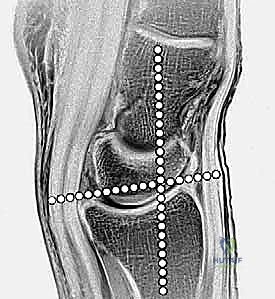

تعد الكعبرة البعيدة بمثابة الدعامة الأساسية الحاملة للوزن في الرسغ، حيث تنقل ما يقدر بنحو 75% إلى 80% من الحمل المحوري من اليد إلى الساعد. أما نسبة الـ 20% إلى 25% المتبقية، فتحملها الزند البعيد والمثلث الغضروفي الليفي (TFCC).

لذلك، فإن أي تغيير، ولو كان طفيفًا، في تشريح الكعبرة البعيدة يؤثر بشكل عميق على ميكانيكا الرسغ، مما قد يؤدي على المدى الطويل إلى تآكل الغضاريف، الألم المزمن، وتطور الفصال العظمي (الخشونة المبكرة). يتكون السطح المفصلي للكعبرة من انحناءات دقيقة تتناسب مع عظام الرسغ (العظم القاربي والهلالي)، ويجب استعادة هذا السطح بدقة متناهية لتجنب المضاعفات المستقبلية.

تُعرف كسور الكعبرة البعيدة بأنها تشمل منطقة الكردوس (Metaphysis)، وتحديداً المنطقة الواقعة ضمن طول السطح المفصلي الذي يعادل أوسع جزء من الرسغ بأكمله. في عياداتنا، نقوم بتقييم هذه الكسور بدقة متناهية بناءً على عدة خصائص رئيسية تحدد مسار العلاج:

- امتداد الكسر: هل هو خارج المفصل (Extra-articular) أم داخل المفصل (Intra-articular)؟